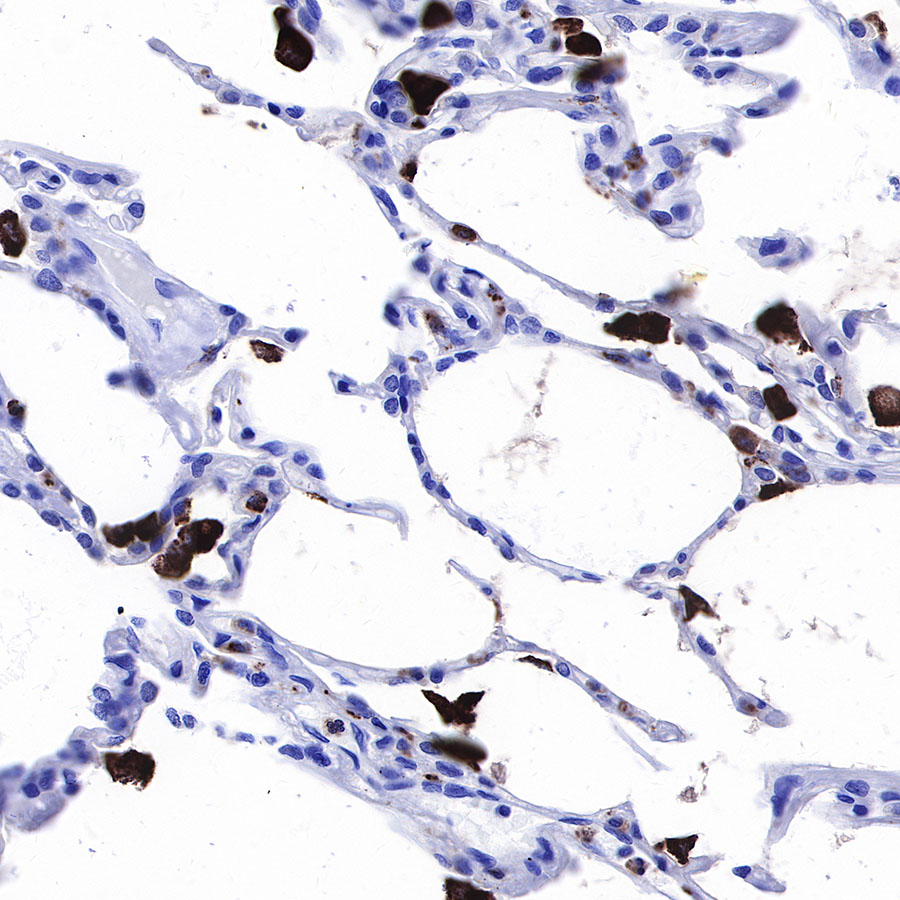

IHC shows positive staining in paraffin-embedded human lung. Anti-CD68 antibody was used at 1/1000 dilution, followed by a HRP Polymer for Mouse & Rabbit IgG (ready to use). Counterstained with hematoxylin. Heat mediated antigen retrieval with Tris/EDTA buffer pH9.0 was performed before commencing with IHC staining protocol.